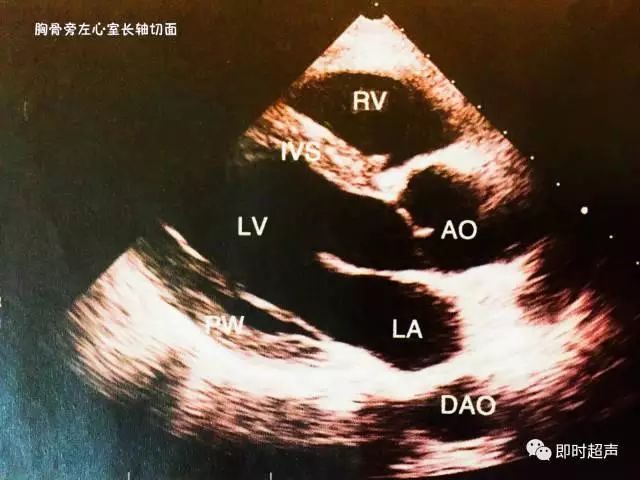

一、胸骨旁左心室长轴切面

主要观察:主动脉、心腔、室间隔和瓣膜的结构和活动情况,是左侧心腔测量的标准切面之一。